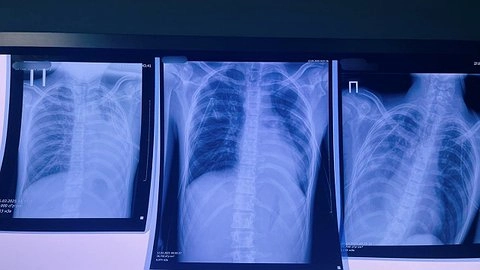

Источник фото: Фото: Минздрав Кировской области

Ситуация в Кирове действительно вызывает обеспокоенность: в больнице оказались 16-летний юноша и 14-летняя девушка, которые, по предварительной инфомации, пострадали от курения вейпов. Известно, что состояние юноши оценивается как тяжёлое, и врачи делают всё возможное, чтобы спасти его жизнь.

Напомним, у 16-летней кировчанки нашли двустороннюю бронхопневмонию из-за курения вейпов.